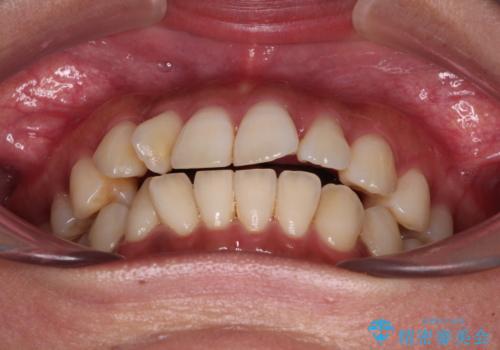

【モニター】上顎前突と奥歯の鋏状咬合 補助装置を用いたインビザライン矯正治療

- 前歯の歯列不正と奥歯の咬みにくさを気にして来院された患者様です。

インビザラインでの矯正治療を希望されていましたが、奥歯の咬み合わせがインビザライン単独では改善困難と判断されたので、補助装置を併用することとしました。

上顎最後臼歯は極端に外側を向いており、下顎骨に対して上顎骨が前方に位置していたため、補助装置により最後臼歯を一気に内側に引き込むとともに、上顎臼歯を後方移動させ、奥歯の咬み合わせが改善した後に、上下インビザラインにより歯列全体を整えていくこととしました。